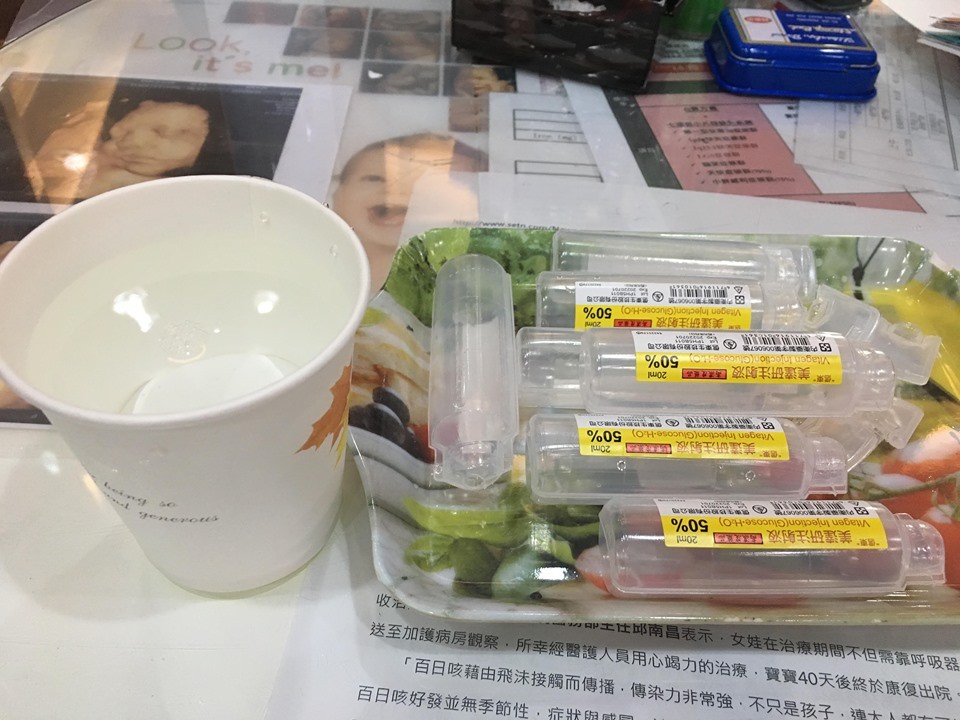

報到後,護理師先幫我抽血,之後遞上了裝滿糖水的紙杯,提醒我要在10分鐘內慢慢喝完它,還補上一句:千萬不要吐出來啊!!!只能搭配少許的開水潤個喉嚨,心想怎麼可能呢? 「故作鎮定喝下,糖水後勁隨之而來,應該說:口中甜味揮之不去,好膩呦。」可能本人平常喝的手搖飲最多只能接受3分糖的那種程度,若妳平常是很愛喝甜的話,應該難不倒各位孕媽咪們喔~其實,身旁的朋友喝過都滿能接受的,就像豐年果糖加水的感覺,只是比較稠一些XD,所以說味道這東西還是見仁見智。